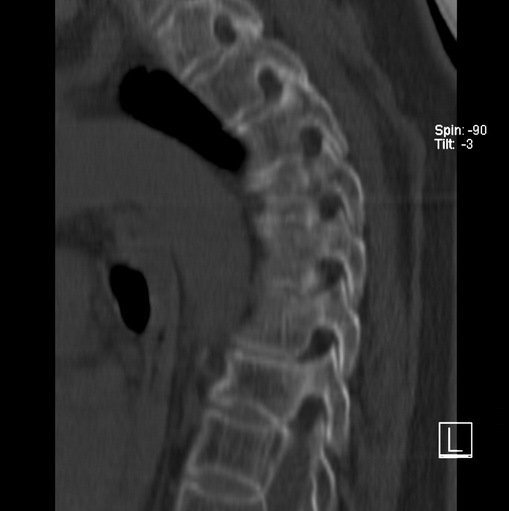

女、73、胸痛、胸闷3个月,无明显外伤病史,x线疑t4、t7陈旧压缩骨折,ct未经明显骨折,请问结论如何报?

老年女性病人,骨质稀疏,有些驼背,t4明显变扁,t7略变扁,椎体边缘无中断,骨小梁排列正常,无嵌插所致致密线。结合无明显外伤史,考虑老年骨质稀疏,慢性压缩改变,正如老年人骨质稀疏椎体呈双凹改变一样。我考虑报:老年骨质稀疏,t4、t7楔形变,脊柱曲度改变(驼背).敬请大家指教。

1)多个胸椎陈旧性压缩性骨折。2)胸椎普遍性骨质疏松。3)胸椎退行性改变。